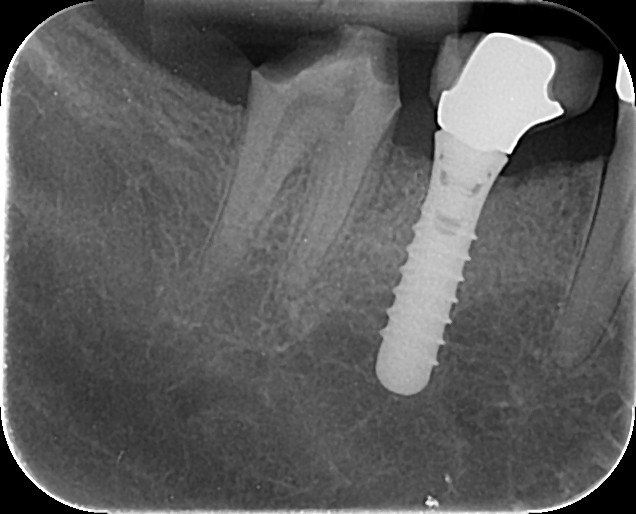

3. What option can be selected regarding the implant seen in this X ray?